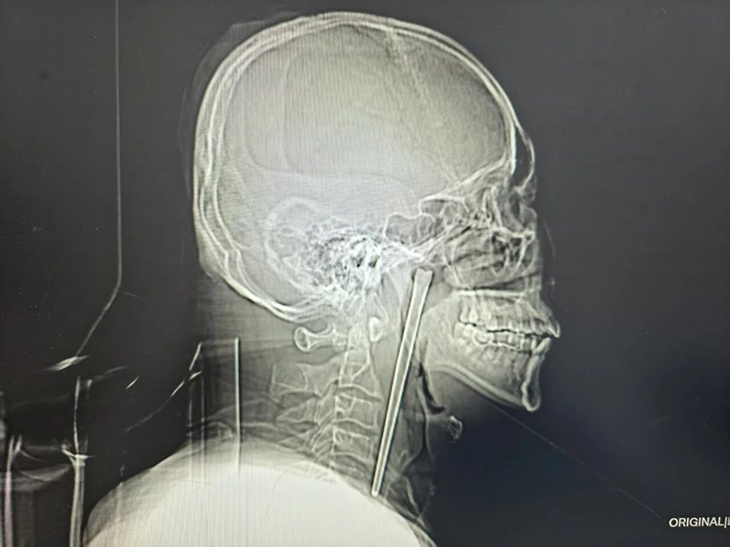

Ảnh chụp X-quang chiếc đũa dài khoảng 12 cm nằm trong cổ họng bệnh nhân. Ảnh: YouTube

Một người đàn ông Trung Quốc đã sống suốt 8 năm với một chiếc đũa kim loại mắc trong cổ họng trước khi được phẫu thuật lấy ra thành công. Theo báo cáo bệnh án được công bố gần đây, bệnh nhân, được xác định là ông Wang, 46 tuổi, đã vô tình nuốt phải một chiếc đũa kim loại dài khoảng 12 cm trong bữa ăn vào năm 2018 khi đang trong tình trạng say rượu. Sau sự cố, ông đã đến cơ sở y tế kiểm tra nhưng từ chối phẫu thuật do lo ngại phải mổ mở vùng cổ.

Nhóm phẫu thuật đã lựa chọn phương pháp can thiệp ít xâm lấn, đưa dụng cụ qua đường miệng để lấy dị vật thay vì tiến hành mổ mở vùng cổ. Ca phẫu thuật diễn ra thành công, chiếc đũa kim loại được lấy ra an toàn.